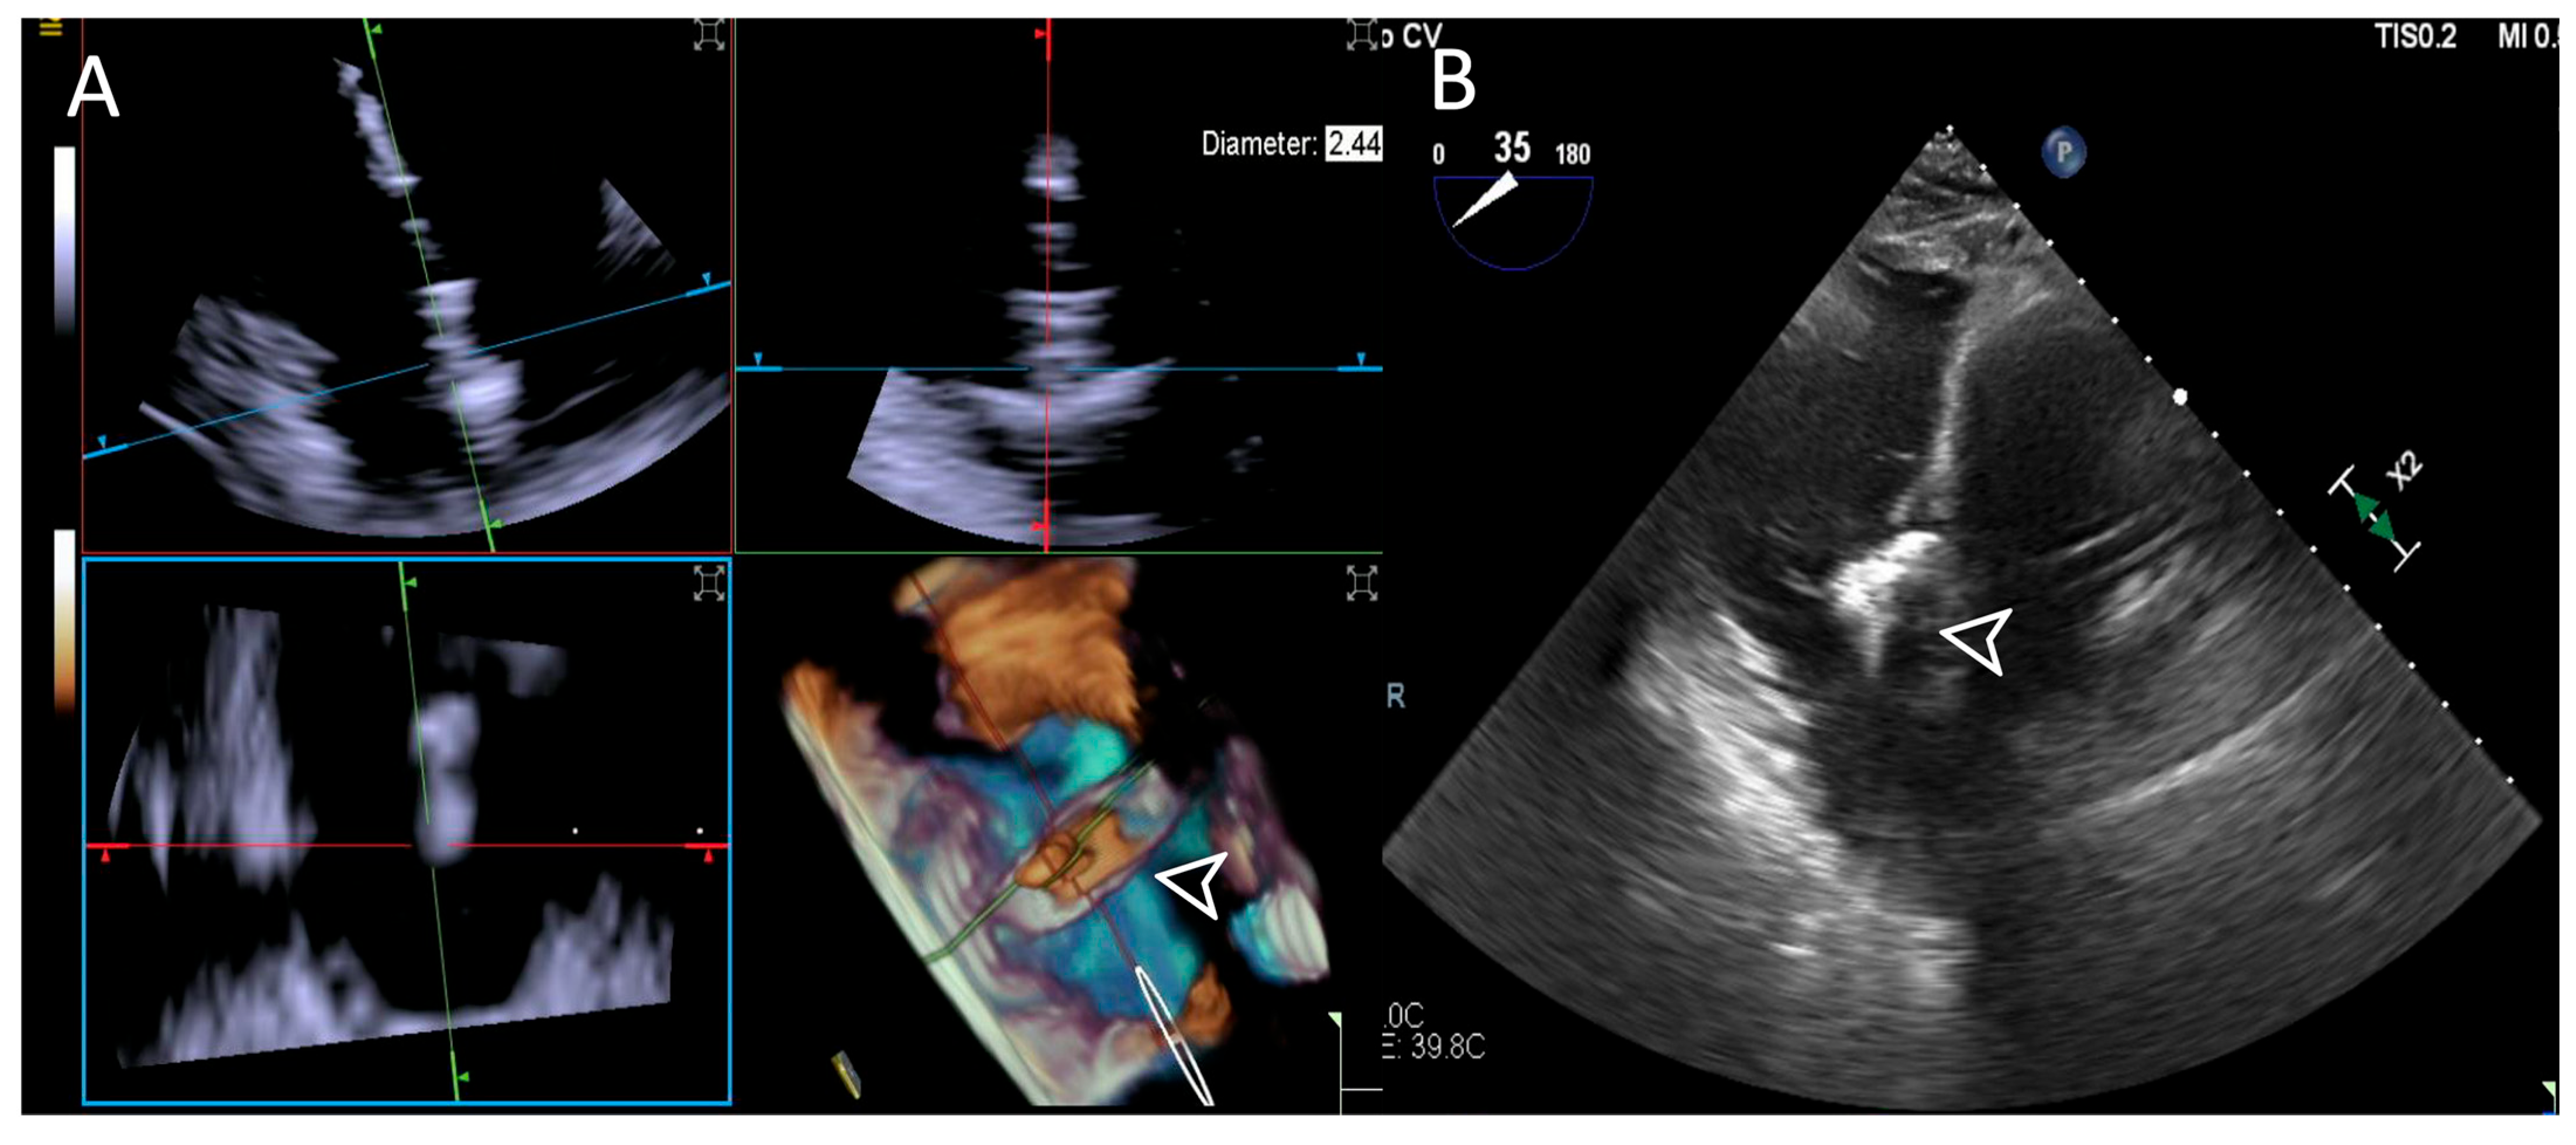

- Step number 3: steering and valve approach.

- Step number 4: ensuring perpendicularity and correct trajectory.